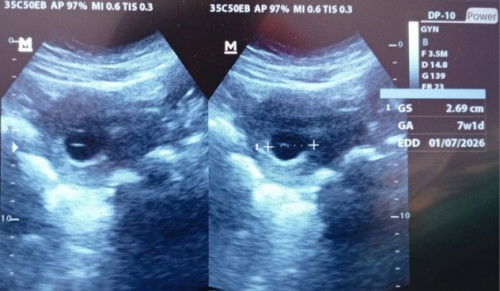

Usg per1 diusia 6week bun.bbrp minggu ada keluhan keluar darah seperti haid menghitung hpht sudah 9week bun tp pas diusg baru 7week,dan bidan bilang bisa terjadi kehamilan BO,bidan menyarankan kuret/atau tunggu 2minggu dengan obat penguat kandungan? Ada yg tau ga bun bagaimanaa,dan semisalkan tidak mau dikuret apa yg terjadi bundaa?ini pertama kehamilan sayađ penantian 10bulanđ« #mohonbantujawabbunda